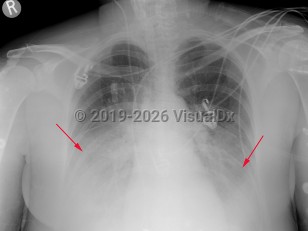

The incubation period is generally between 2-10 days, but cases with incubation periods as long as one month have been reported. A prodromal illness consisting of headaches, myalgias, weakness, diarrhea, and abdominal pain may occur. These symptoms may suggest a viral illness and lead to a misdiagnosis. Cough, shortness of breath, pleuritic chest pain, and fever (in some cases, 40°C [104°F] or higher) may develop. Mental confusion may be present. Clinical examination findings are nonspecific and may include focal rales or signs of lung consolidation. The viral-like prodrome that does not progress to pneumonia is also referred to as Pontiac fever and is self-limited. Pontiac fever has been recognized only during outbreaks of legionellosis.